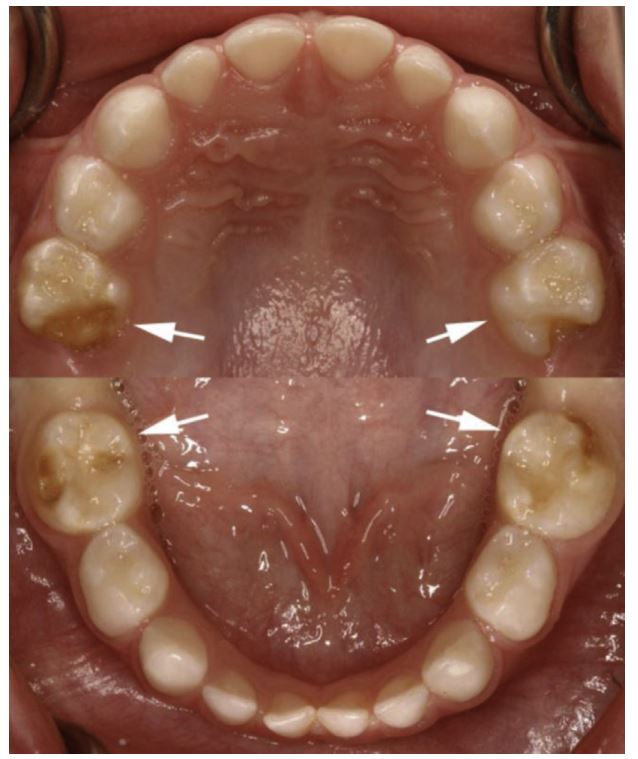

Sâu răng liên quan đến thiểu sản R5 sữa (PSMH-C) xuất hiện ngay sau khi R6 mọc lên, và đôi khi nó có thể là dấu hiệu đầu tiên của chứng giảm khoáng hóa răng cối – răng cửa (molar-incisor hypomineralization – MIH) (liên quan đến R6 và răng cửa vĩnh viễn hàm trên).

Loại hình sâu răng thứ ba, ít phổ biến hơn cả, là sâu răng có liên quan đến thiểu sản men ở bốn R5 sữa (Hình 4).

Trẻ sâu PSMH thì thường không thấy sâu răng ở vị trí nào khác. Sâu răng loại này thường xuất hiện sau khi R5 sữa mọc lên, tầm khoảng 23 đến 33 tháng tuổi.